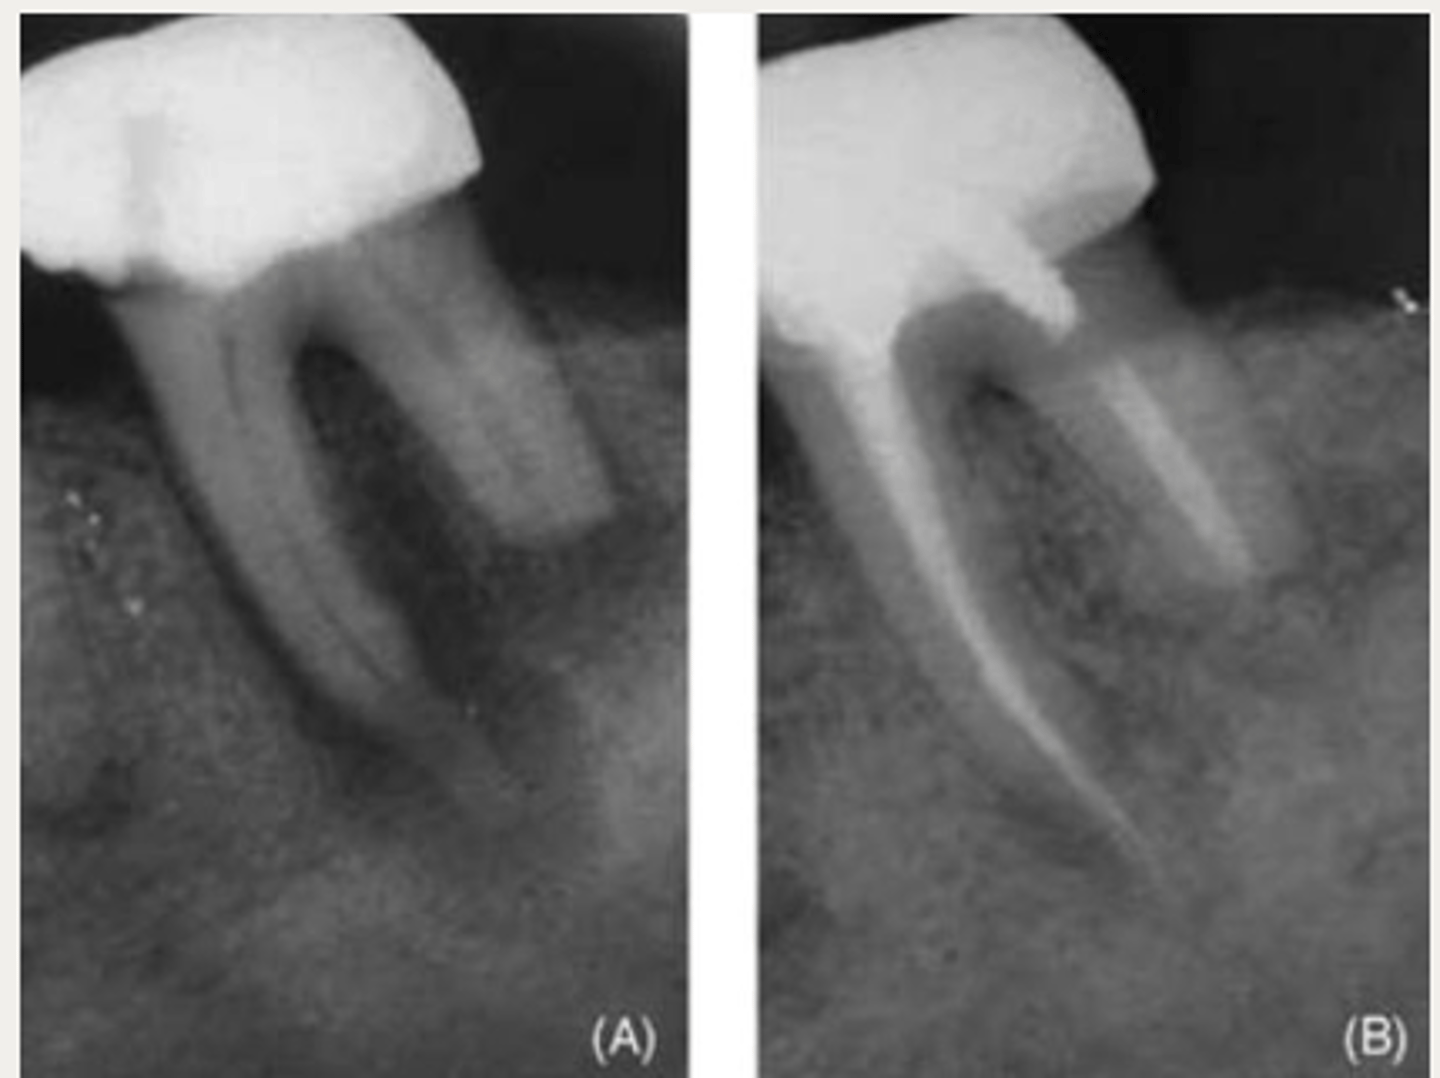

External Replacement Resorption/Ankylosis

Which type of resorption?

- Fusion of cementum or dentin with alveolar bone

Which type of resorption>

- Damage to PDL ⇒ stimulus for surrounding bone to activate osteoclasts and begin resorbing cementum/dentin and replacing it with bone tissue

- Almost always due to trauma (luxation, intrustion, avulsion, replantation)

ID the type of resorption:

CLINICAL

- Characteristic metallic sound on percussion

- May appear infraoccluded in developing dentition

- Lacks physiologic mobility of normal teeth

- May not respond to sensibility testing

RADIOGRAPHIC

- Absence of lamina dura/PDL

- Bone trabeculation occupying previous root surface

- CBCT is often helpful to assess the full extent

Patient presents with a metallic sound on percussion, infraoccluded appearance in developing dentition and may not respond to sensibility testing. What is the most likely diagnosis?

Patient presents with these radiographic findings. What is the most likely diagnosis?

- Absence of lamina dura/PDL around lesion.

- Bone trabeculation occupying previous root surface.